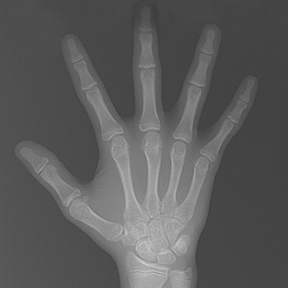

얼굴 골격의 성장에 문제가 있는지를 파악하기 위한 적절한 시기는 초등학교 입학 전인 6-7세경입니다. 이때는 유치에서 영구치로 교환되는 시기로서 부정교합 여부가 결정되는 중요한 시기이므로 이 시기를 잘 관찰하여 부정교합을 예방하는 것 또한 중요합니다. 교정의 정확한 시기는 6개월 간격으로 치과에 정기적으로 내원하여 성장 분석을 받은 후 결정하는 것이 좋습니다.